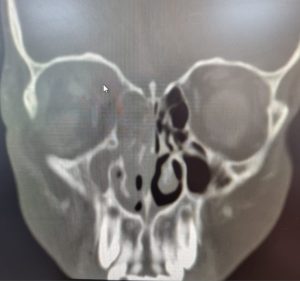

وأكدت الصحة في جدة أن المريض حضر لطوارئ مستشفى الملك عبد العزيز كحالة انقاذ عضو يشتكي من الم حاد و احمرار و انتفاخ شديد في العين اليمني منذ خمسة ايام ، و تم عمل الفحوصات و الأشعة المقطعية اللازمة التي اظهرت التهاب شديد في الجيوب الأنفية من الجهة اليمني ادت الي وصول خراج (صديد) لمقله العين اليمني.

وبينت أن الفريق الطبي المعالج قرر إجراء تدخل جراحي عاجل وإجراء عملية دقيقة بالمنظار للجيوب الأنفية و تنظيف كامل لكل الاحتقانان و الالتهابات و الخراج (الصديد) لجميع الجيوب الأنفية للجهة اليمني و الجهة الداخلية للعين اليمني ، ليتم بعدها نقل المريض لقسم التنويم ومتابعة الحالة من قبل الفرق التمريضية لحين استقرار الحالة وخروجها بالسلامة من المستشفى